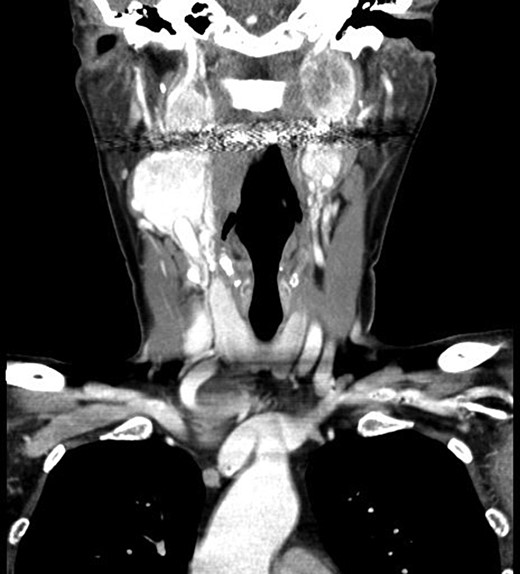

Computer tomography imaging (Fig. 1) revealed multiple bilateral PGLs extending from the carotid bifurcations to the base of the skull. The tumors were engulfing the vagus nerve, making them inoperable at the time. The PGLs were deemed nonfunctional by laboratory assessment of urine and plasma metanephrines and catecholamines. Genetic analysis revealed a SDH-D subunit mutation, an autosomal dominant mutation, resulting in markedly elevated risk of PGL tumors, especially bilaterally.

Computed tomography, coronal view, shows multiple bilateral PGLs extending from the carotid bifurcations to the base of the skull, engulfing the vagus nerve.